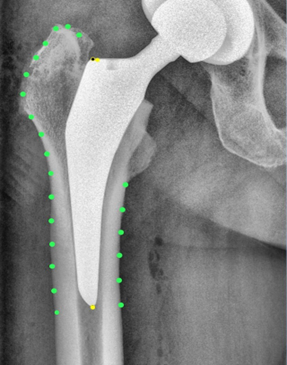

Hip stem migration (subsidence) was evaluated on anteriorposterior radiographs of the pelvic in a standing position with a film-focus-distance of 115 cm performed 5 days, 3 months and two years postoperative. The validated software “FXA” of the independent imaging core lab (RAYLYTIC, Leipzig, Germany) was used [26-28]. The software matches two images (24 months and 3 months vs. 5 days postop) using a normalized 2D grayscale cross-correlation algorithm in an iterative process using the evolutionary optimization algorithm CMA-ES [29]. Moreover, the radiographs were analyzed for radiolucent lines around the stem. The radiographs were analyzed retrospectively. The following parameters were measured on the postoperative radiographs (Figure 2,3): The Canal Flare Index (CFI), the Canal Fill Ratio (CFR), the Stem Angulation (SA) and calculated as potential influencing factors for subsidence as well as the clinical parameters: gender, weight, BMI, age and stem size.

Figure 3b: Case example with FXA software to analyze the subsidence. Fig. 3a: five days postoperative, Fig. 3b: two years postoperative